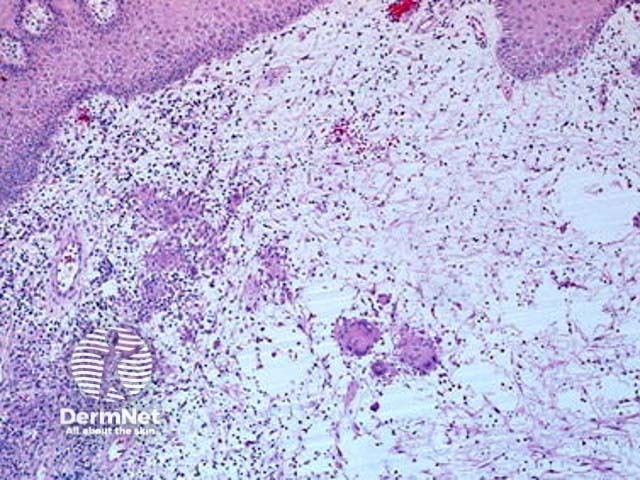

Metastatic Crohn disease is characterised by a dermal granulomatous infiltrate composed of epithelioid histiocytes (figures 1-5). There is an associated infiltrate which is mainly lymphocytic but may be rich in eosinophils. The granulomas may encroach on the epidermis (figure 1). Massive oedema may be seen (figure 2). Ulceration of the overlying epidermis is a common feature (figure 4).

Figure 2